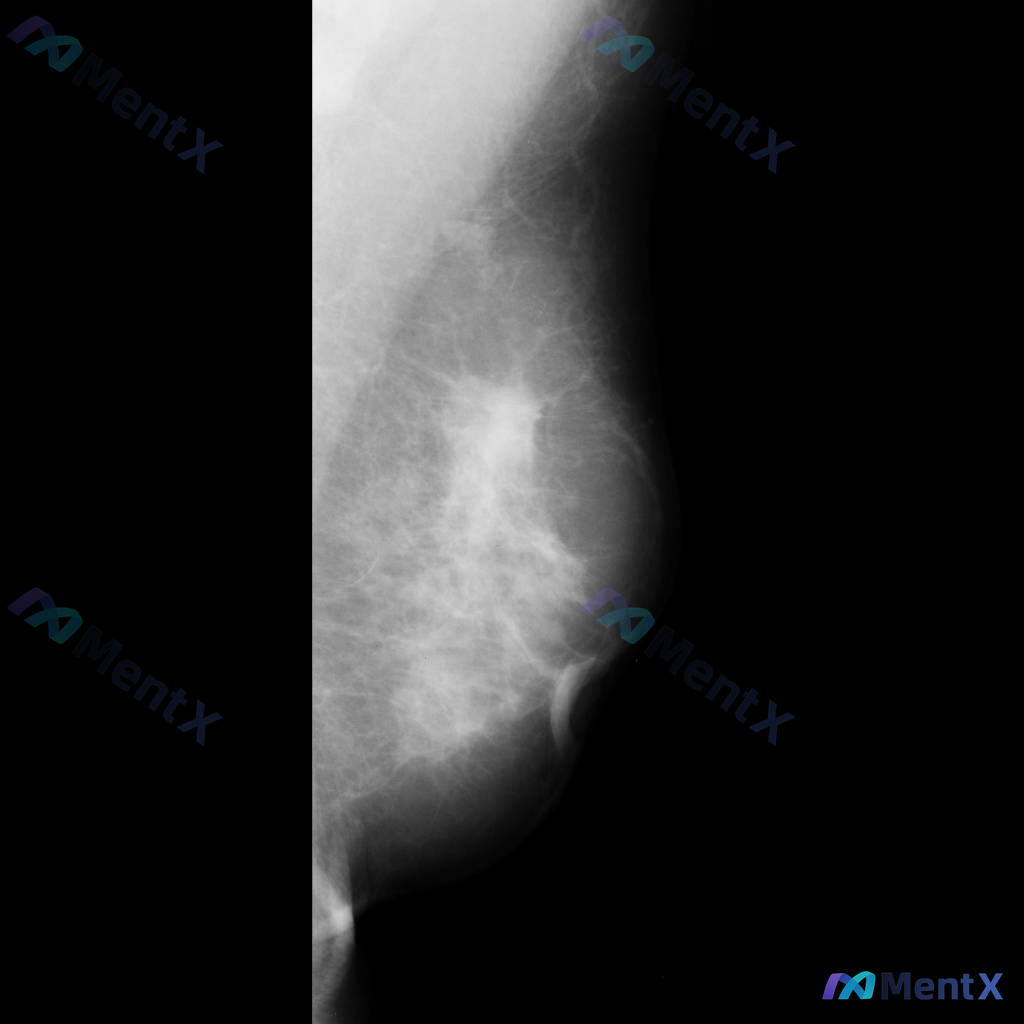

整理到一张乳腺钼靶影像的分析资料,先和大家同步一下核心表现: - 乳腺构成:不均匀致密型 - 主要异常:在乳腺中央偏上区域可见一个不规则形高密度肿块,边缘有毛刺样改变;围绕这个高密度影,周围的乳腺小叶和导管结构紊乱,向病灶中心牵拉。 目前暂时没有更多临床病史、查体或其他检查补充。想先问一下大家:单看...

整理到一张乳腺钼靶影像的分析资料,大家可以先基于现有信息讨论一下。 基本影像学表现 - 可见形态不规则的致密区域,伴有结构扭曲和模糊边缘 - 背景乳腺腺体呈 BI-RADS B/C 型(致密性增加) 目前从影像上看,存在几种可能的方向,想听听大家的第一判断:单看这组影像学表现,你会先考虑哪一种异常方...

整理到一份乳腺钼靶的影像资料,大家可以一起讨论下: 主要影像表现:右侧乳腺后方(近胸壁处)可见一处局灶性不对称致密影,密度高于周围正常乳腺组织,边界模糊,同时伴有周围乳腺组织结构扭曲。 目前影像科考虑这处异常有可疑特征,需要进一步鉴别。 想问问大家,单看这组描述的话,第一反应会先往哪个方向考虑?后续...